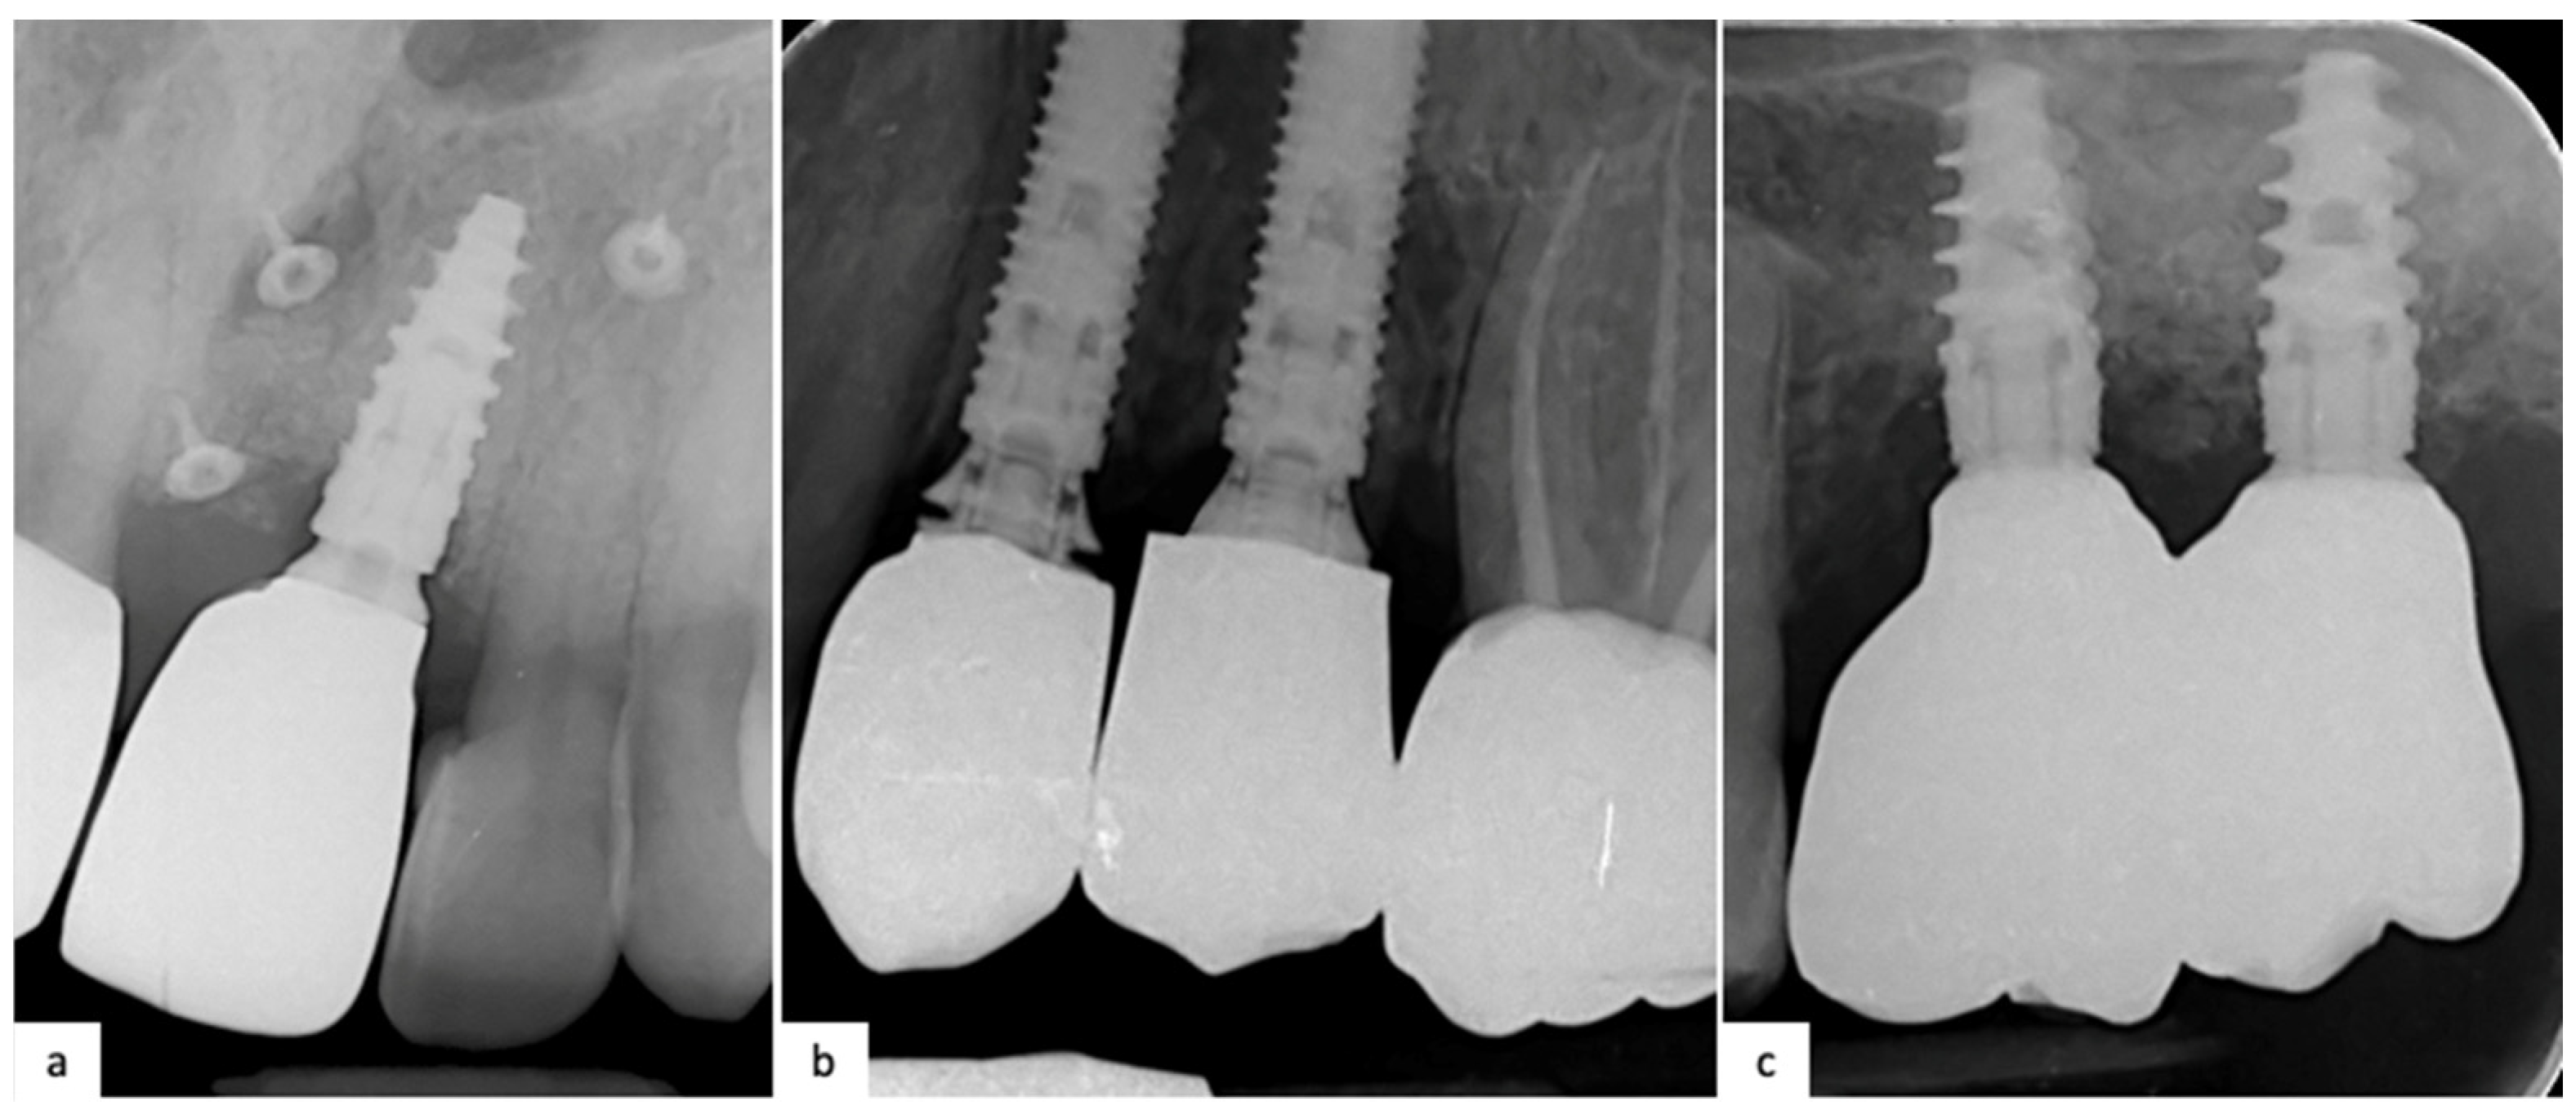

The impression was conventional, with an analog material such as hydrophobic polyvinylsiloxane, as in the previous arm. All the models were plaster cast. Definitive crowns provide a metal ceramic crown made by chrome–cobalt alloy substructure with feldspathic ceramic layering. No digital step was performed. A clinical case of a 1.4 (NobelReplace) with fully analog workflow is reported below (Figure 3).

Figure 3. (a) Preoperative clinical situation showing a vertical fracture of 1.4; (b) Intraoral Rx showing no marginal implant–abutment gap; (c) Vestibular view of final restoration; (d) Occlusal view of final restoration.